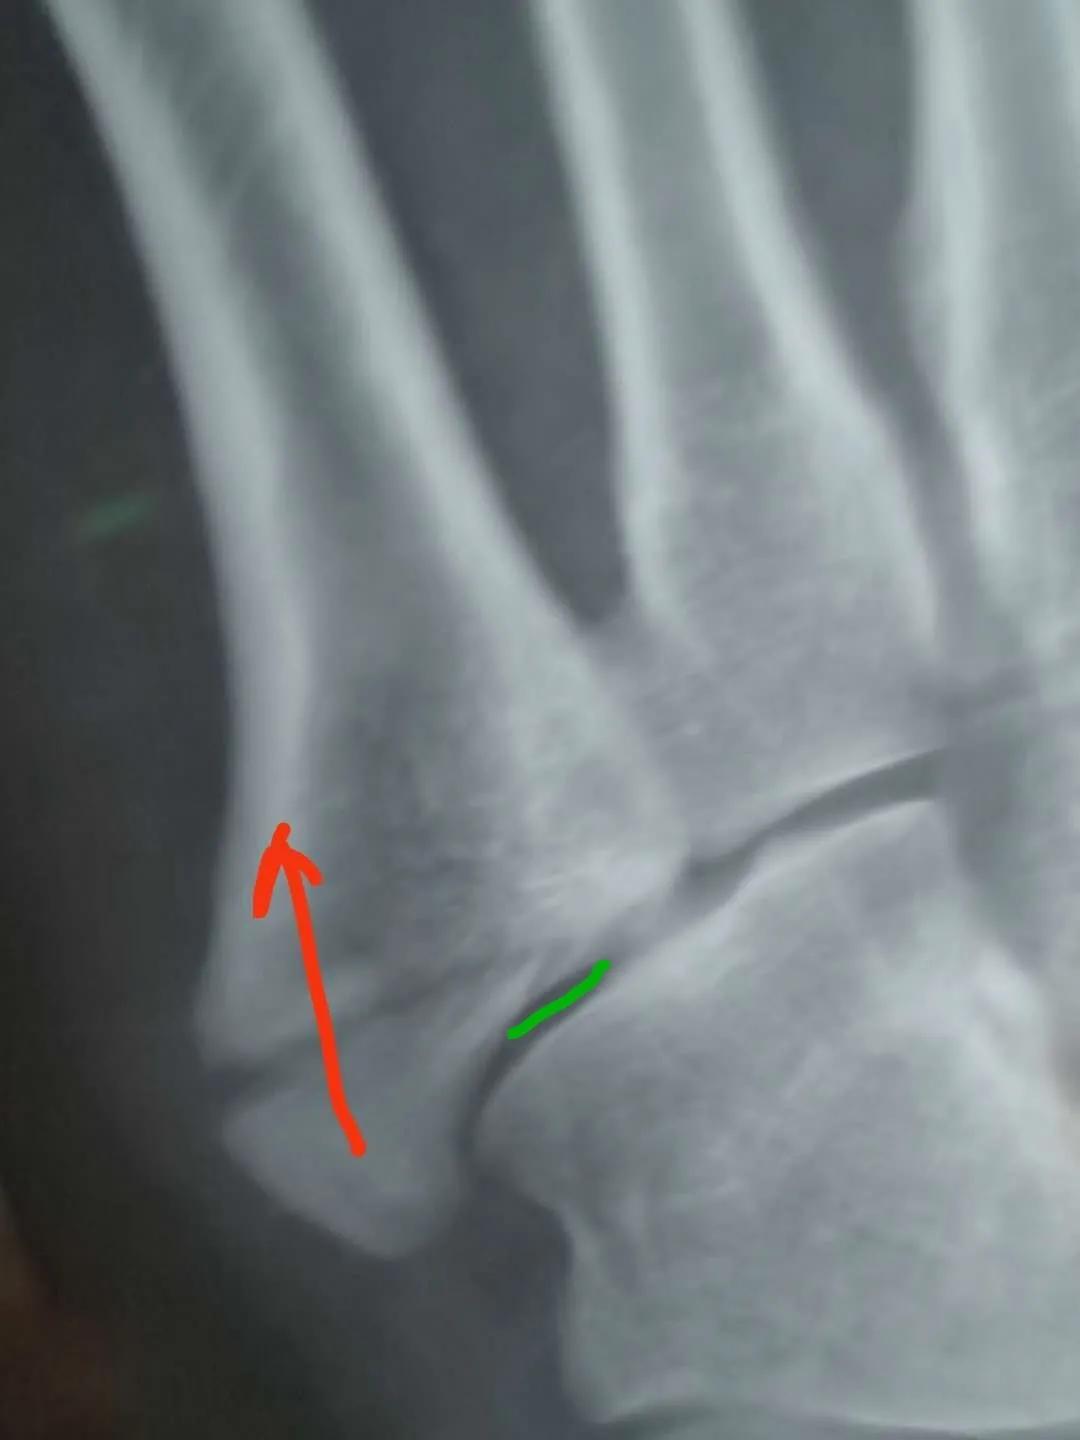

看片子骨缝比较大了,有点移位,而且中间崩碎了一块,一直找不到,后来复查才发现那个碎片掉落在骨缝当中了

此图可以看见中间碎片在骨缝里面

6月底复查,骨缝小的地方已经有了一点愈合的痕迹,医生说如果手术可以在红线位置打个钉子,但是现在打会破坏内部已经开始愈合的部分,建议继续保守……